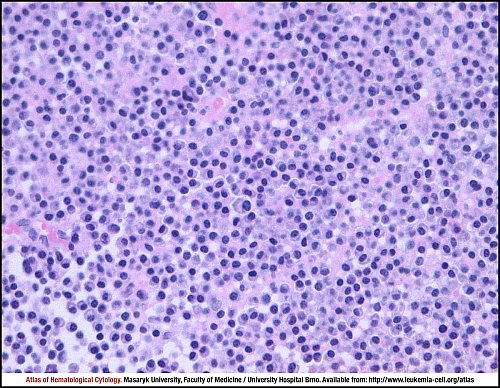

Микропрепараты: Лимфогранулематоз и Нодулярный Склероз